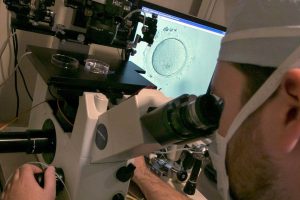

Les Pays-Bas viennent d’autoriser la production d’embryons à des fins de recherche scientifique pour résoudre les problèmes d’infertilité, les échecs de la reproduction médicalement assistée ou prévenir les maladies héréditaires. […]

8 juin 2016 - Dans les médias, Recherche